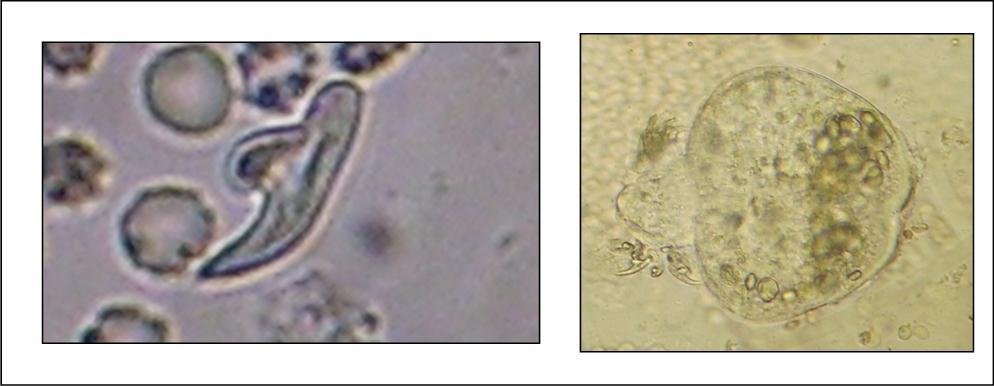

A 27 years-old male patient was admitted with 1 month history of headache, fever, short term memory lack, aphasia, right hemiparesis and seizures. He had liver hydatid cysts excised 8 years before and was treated with adjuvant medication (albendazole). The neurological examination revealed right central third cranial nerve palsy and hemi paresis, with Babinski sign positive, aphasia and papilledema on ocular fundus. The Glasgow Coma Scale was evaluated to 10/15 (E:3; V:1; M:6). A brain CT scan showed a large left temporoparietal intracerebral multiple and calcified hydatid cysts, important mass effect with midline shift about 7 mm following by an obstructive hydrocephalus (Figure 1). Other cysts were found in thalamic region (Figure 2). The Thoraco-abdominal CT scan showed multiple intra peritoneal hydatid cysts (Figure 3). A left temporo parietal craniotomy was performed in emergency. After corticectomy, using Arana-Iniguez technique, the appearance of the capsule suggested infected hydatid cysts with a purulent material which was aspirated. Numerous hydatid cysts were lifted away and several daughter vesicles were carefully removed without rupture (Figure 4). Macroscopically, the abscess wall appeared to be thick, calcified and tightly attached to lateral ventricular, so it could not be removed. The deep cyst overlying the third ventricle was left.in place. Microscopic examination demonstrated live scoleces, protoscoleces and multiple hooks. These findings are consistent with hydatid cyst (granulosis ecchinococcus) (Figure 5). Bacteriology examination found several white blood cells in the pus (neutrophilia) and infection by streptococcus pneumonia. This was consistent with infection. After surgery, the patient had medication (albendazole, specific antibiotherapy and phenobarbital). The inflammation assessment in the blood showed leukocytosis, a high C-reactive protein rate and increased erythrocyte sedimentation rate. Post operative CT scan was performed and showed the residual calcified capsule and decreased ventricular size (Figure 6). Clinical improvement was achieved after treatment. One month after the initial diagnosis, CT scan of the brain showed no recurrence and a physical examination revealed a neurologically intact, fully functional patient and eyes fundus normal. He was discharged and went to abdominal surgery two months later with complete intra abdominal cysts removal. Albendazole treatment was continuing for six months and radiological exploration was performed by brain MRI with spectroscopy at three and six month later. This showed that infection had resolved and the deep cyst overlying the third ventricle is less spherical (Figure 7, Figure 8). Four years later, the outcome was good.

Figure 5.photomicrograph showing hydatid scoleces and their hooks after centrifugation (original magnification, x100).